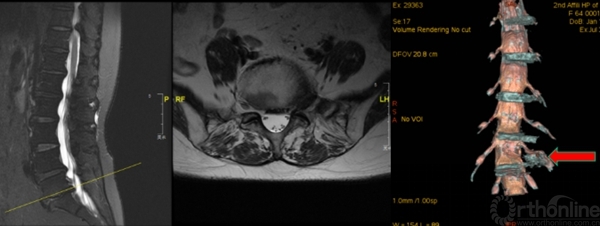

3D-MRI:对一些特殊类型的椎间盘突出(如极外侧腰椎间盘突出)可起到更加准确的诊断作用

怀疑融合临近节段极外侧突出,选择性神经根阻滞术明确诊断

介入诊断技术:选择性神经根阻滞技术、椎间盘造影技术等,不仅可以从患者的主观感受进一步精准诊断,同时对脊柱内镜手术的疗效可以起到预测作用。